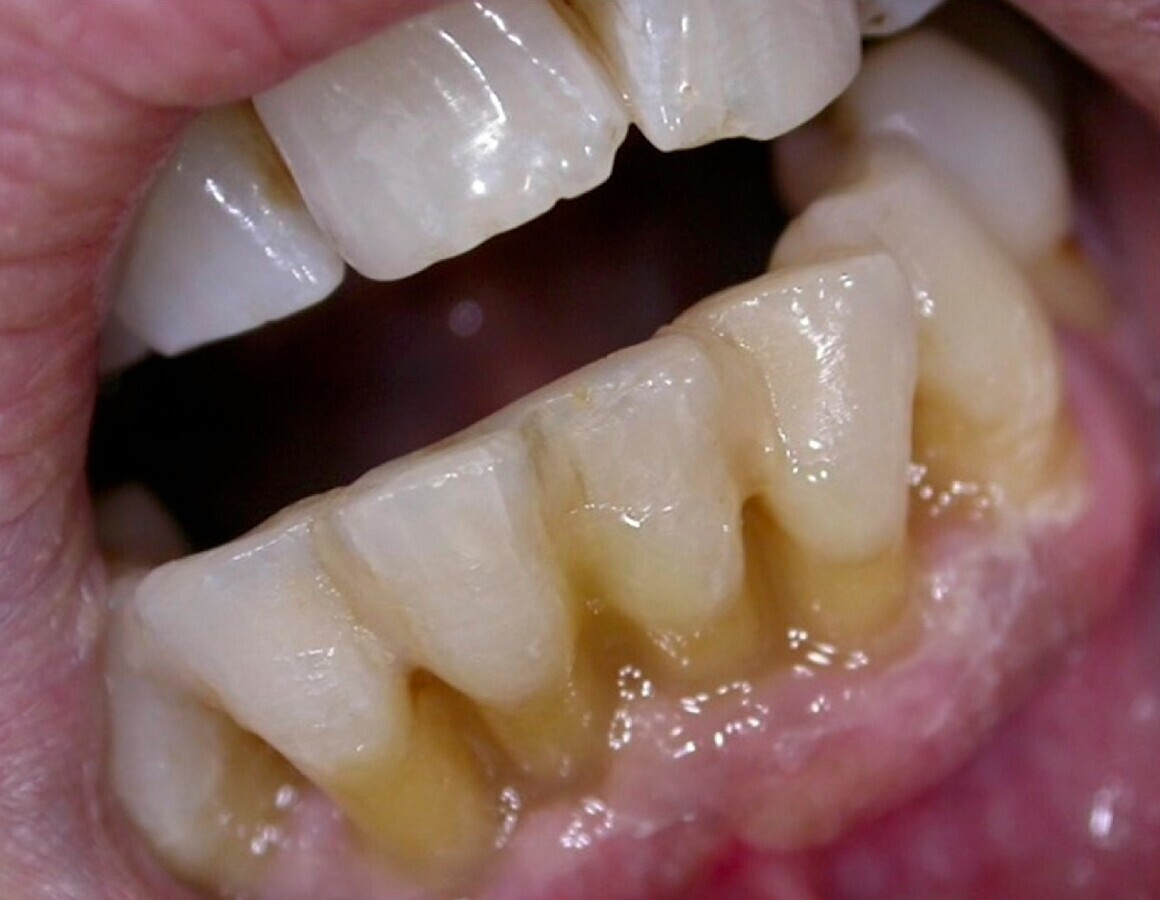

Así pues, antes de plantear cualquier medida higiénica, se tiene que valorar el estado del paciente y su capacidad para poder proceder al mantenimiento de su higiene oral, ya que podemos encontrar desde paciente mayores perfectamente válidos hasta pacientes frágiles o con distintos grados de dependencia e incapaces de mantener sus cuidados higiénicos personales mínimos diarios ni tampoco los bucodentales (Fig. 1).

Figura 1. La higiene deficiente es habitual en este colectivo por diversas razones, entre ellas problemas médicos; de hecho, existe una asociación directa entre el grado de deterioro mental y el deterioro de la higiene oral.

Una vez revisados por el odontólogo y realizado el diagnóstico de sus necesidades, se le realizarán los tratamientos necesarios (empezando por la higiene-detartraje y/o raspados, extracciones de dientes no recuperables y tratamientos de caries si las hubiera). Posteriormente, el odontólogo valorará al paciente en función del “riesgo percibido” para poder incluirlo en un protocolo de mantenimiento, programando así las visitas futuras, con una frecuencia que dependerá de su situación de salud general (Figs. 2, 3 y 4).

Figura 2. Paciente de bajo riesgo de caries, con una higiene aceptable. En casos de riesgo bajo de caries se recomienda realizar una revisión cada 6 meses.

Figura 3. Paciente con riesgo moderado de caries, higiene deficiente, ausencia de dientes y obturaciones (historia de caries). En casos de riesgo moderado de caries se aconseja realizar revisiones cada 3 a 4 meses.

Figura 4. Paciente de alto riesgo, con ausencias dentales, portador de prótesis removible, obturaciones, caries activas y presencia de placa. En casos de alto riesgo se deben realizar los tratamientos pertinentes y las revisiones cada 2 a 3 meses.